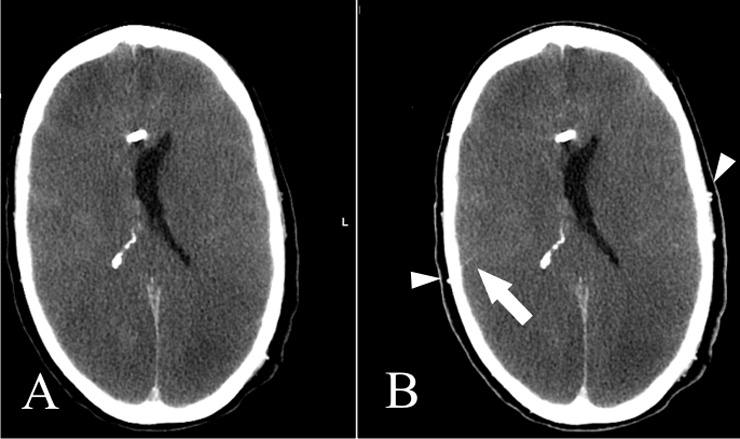

Figure 3

Non-contrast CT (A) and venous-phase CT (B): Opacification of the superficial temporal artery indicates sufficient contrast injection (Arrowheads). Note also opacification of an M4 segment artery on the right, a marker of some residual cortical perfusion. In this case, circulatory arrest could not be confirmed.